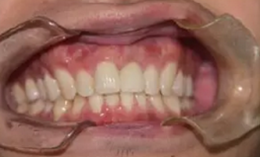

永久修復(fù)

永久修復(fù)后3年進行回訪,種植體骨結(jié)合穩(wěn)定,美學(xué)效果良好。

圖14 永久修復(fù)3年后的回訪